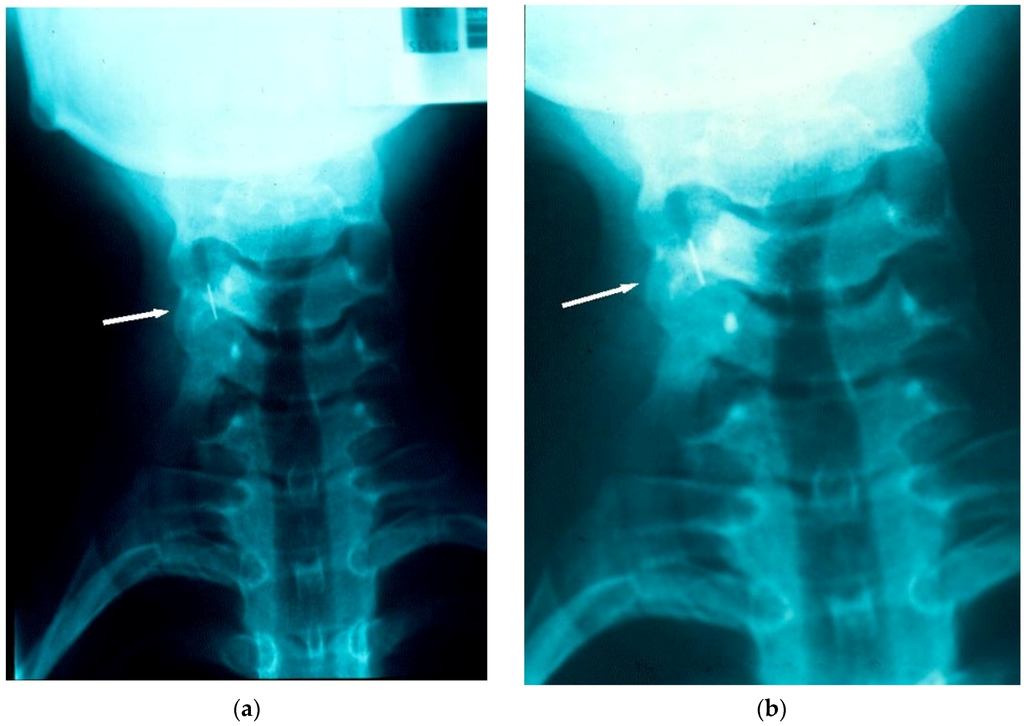

Radiographic investigations were carried out as a matter of urgency and confirmed that the archwire fragment had lodged in the right piriform recess (Figure 1a,b).

(a) Radiograph taken within 15–20 min of the chairside incident, locating the archwire fragment to the right piriform recess; (b) Radiograph taken within 15–20 min of the chairside incident, locating the archwire fragment to the right piriform recess.

The patient was transferred immediately to the Region’s main General Hospital, which was provided with a sample of an equivalent archwire. Approximately three hours later, under general anaesthesia, the patient underwent endoscopic retrieval of the fragment. The archwire fragment could not be found on exploration of the piriform recess, larynx or oesophagus, and further radiographs were taken. It was found that, in the three hour period between the incident and presentation to the General Hospital, the archwire fragment had relocated and had been ingested. Once this was confirmed, no further operative retrieval procedure was pursued, and instead, the patient was monitored. A hospital stay (3.5 days) was necessary due to a post-operative pyrexia and post-instrumentation discomfort. During this in-patient period, serial tracking radiographs confirmed that the orthodontic archwire fragment had passed safely and uneventfully through the gastrointestinal tract (Figure 2 and Figure 3). Following discharge there was rapid recovery to full health. Orthodontic treatment was resumed and completed successfully without further incident.

This case report highlights common issues. The archwire fragment was ingested, rather than aspirated and passed through the GIT without incident. However, at the time of the incident, these two factors could not have been determined or predicted. Immediate retrieval was not possible as the archwire fragment could not be located in the oro-pharyngeal region. Once radiographs confirmed that the archwire fragment was in the piriform recess, retrieval was considered imperative. Initial radiographs, taken approximately 15–20 min after the incident had arisen, suggested that impaction had occurred. The time interval of approximately three hours before the endoscopic retrieval could be undertaken in a General Hospital facility (geographically removed from where the incident occurred) proved significant. Radiographic views confirmed that ingestion of the archwire fragment had occurred in the intervening period.